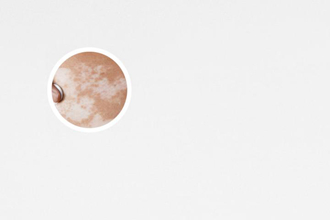

白斑的早期癥狀圖

白斑的早期癥狀較顯然的特征就是皮膚顏色的改變。在白斑部位,皮膚的色素會(huì)逐漸消失,形成白色或乳糜色斑塊。初期白斑一般較小,局部色素消失程度也相對較輕。

隨著白斑的形成,皮膚上會(huì)出現(xiàn)不均勻的顏色變化。白斑通常會(huì)呈現(xiàn)為白色或乳白色的斑塊,邊緣有時(shí)會(huì)出現(xiàn)清晰界限,有時(shí)則比較模糊。特別是在暴露于陽光下時(shí),白斑的顏色差異可能更加顯然。